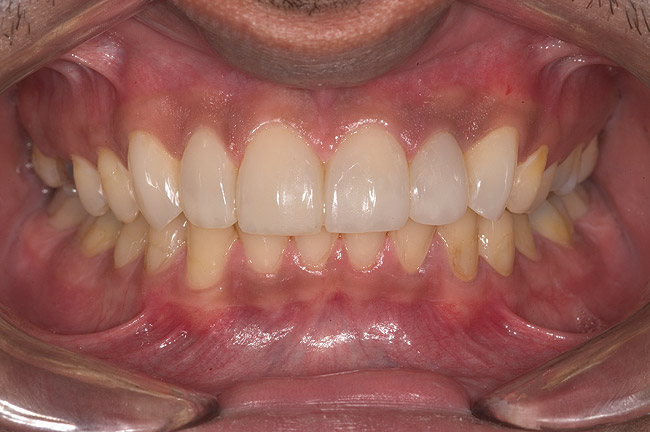

Figure 4  Preoperative smile view.

Figure 4

Figure 14  Postoperative smile.

Figure 14

Figure 15  Maximum intercuspation (MIP) after restoration of the lost palatal anatomy.

Figure 15